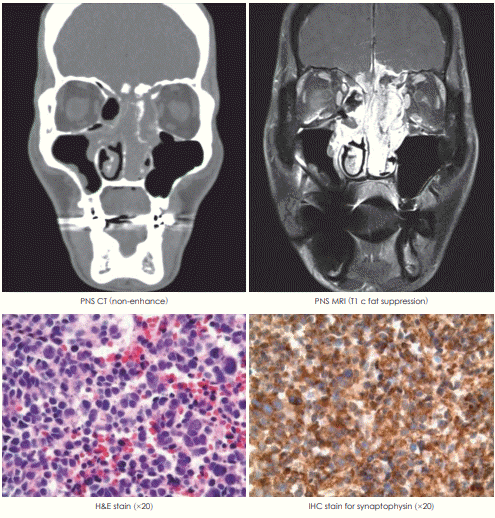

55세 남자 환자가 코막힘과 농성 비루, 후각저하를 주소로 내원하였다. 환자CT, MRI소견은 아래와 같다. Pathology에서 small round cell tumor로 보여 시행한 synaptophysin에 대한 immunohistochemical stain(IHC)에서 양성 소견을 보였다. 현 상태에 대한 설명으로 옳은 것을 고르시오.

해 설 Esthesioneuroblastoma(olfactory neuroblastoma)에 대한 설명이다.

① 일반적으로 방사선 치료에 반응이 좋다.

② 경부 임파선 전이는 20~25%의 환자에서 존재한다.

③ Adenoid cystic carcinoma에 대한 설명이다.

④ SCC에 대한 설명이다.